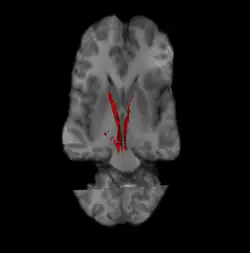

![]() Nigrostriatal pathway (Left and Right in red). | |

The nigrostriatal pathway is a bilateral dopaminergic pathway in the brain that connects the substantia nigra pars compacta (SNc) in the midbrain with the dorsal striatum (i.e., the caudate nucleus and putamen) in the forebrain. It is one of the four major dopamine pathways in the brain, and is critical in the production of movement as part of a system called the basal ganglia motor loop. Dopaminergic neurons of this pathway release dopamine from axon terminals that synapse onto GABAergic medium spiny neurons (MSNs), also known as spiny projection neurons (SPNs),[1][2] located in the striatum.